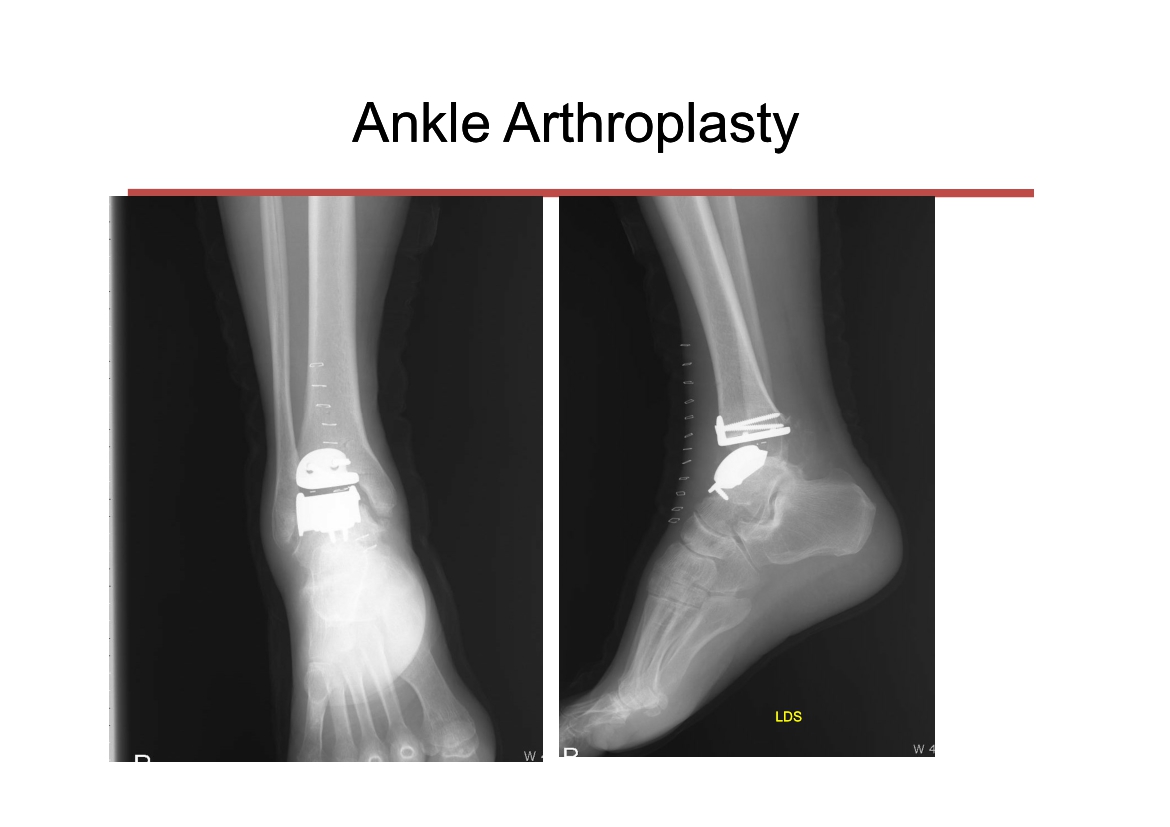

윤정로 병원장님 퇴행성 관절염 치료 자료

윤정로 병원장님의 퇴행성 관절염 치료 관련 자료 입니다.